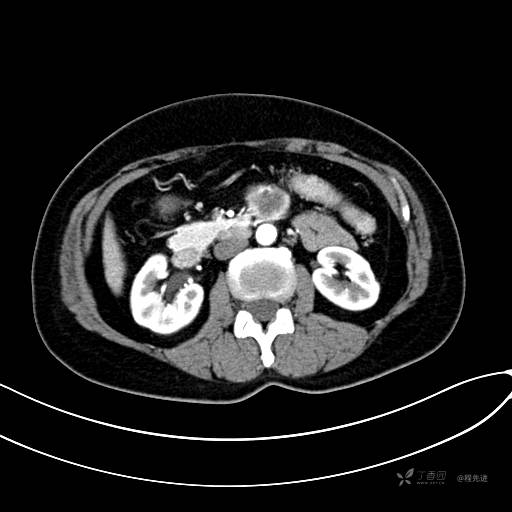

CT增强动脉期